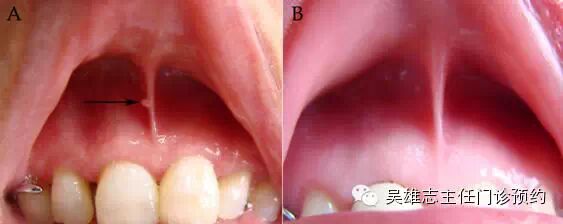

患者上唇系带照片均拍摄于CT, MRI,PET-CT或活检检查后1月以内,上唇系带处出现结节或隆起者定为阳性病例,反之上唇系带平滑者为阴性(图1)。选择较明显阳性病例取活检送病理以明确上唇系带结节性质。

图1 上唇系带状态

A 上唇系带阳性 B 上唇系带阴性